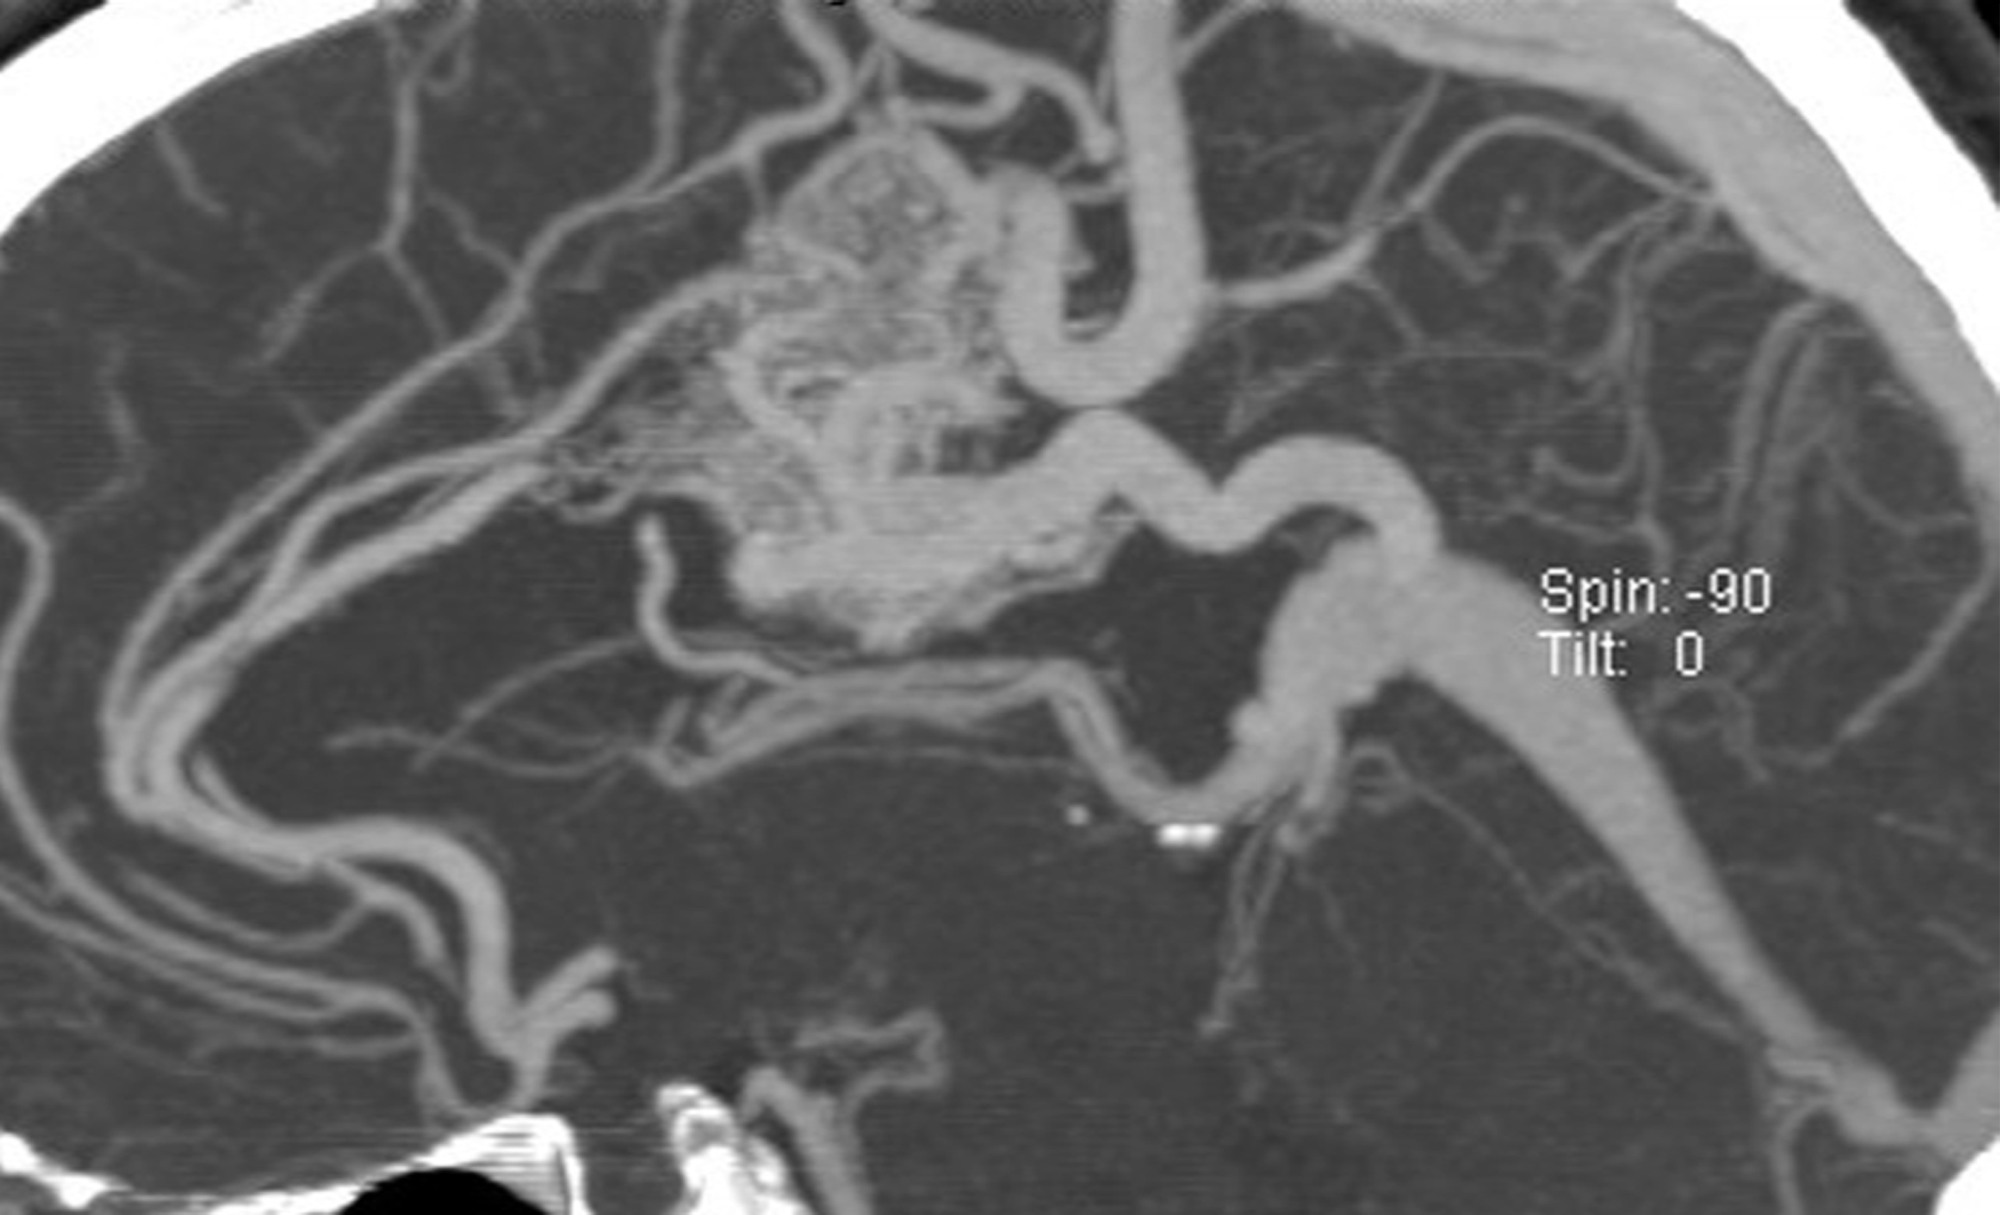

It is not clear why AVM’s form, but some researchers believe that these tangles of vessels are present from birth (a congenital disorder). Several rare genetic diseases are associated with AVM’s. AVM’s classically appear as a complex tangle of abnormal thinly-walled vessels called a “nidus”. A distinguishing feature is that they occur anywhere within the brain or spinal cord. AVM’s are rare, occurring in about 0.2% of the population (200 cases per 100,000 people).

While a CT (computed tomography) or MRI (magnetic resonance imaging) test of either the brain or spinal cord will typically first detect these lesions, catheter-based diagnostic (cerebral or spinal) angiography is essential to fully understand and characterize the AVM. This evaluation allows your doctor to determine your future risk of symptoms and your treatment options. Treatment of an AVM depends on whether symptoms are present or not, how large the lesion is, where it is located and a host of other features only determined by the diagnostic (cerebral or spinal) angiogram.